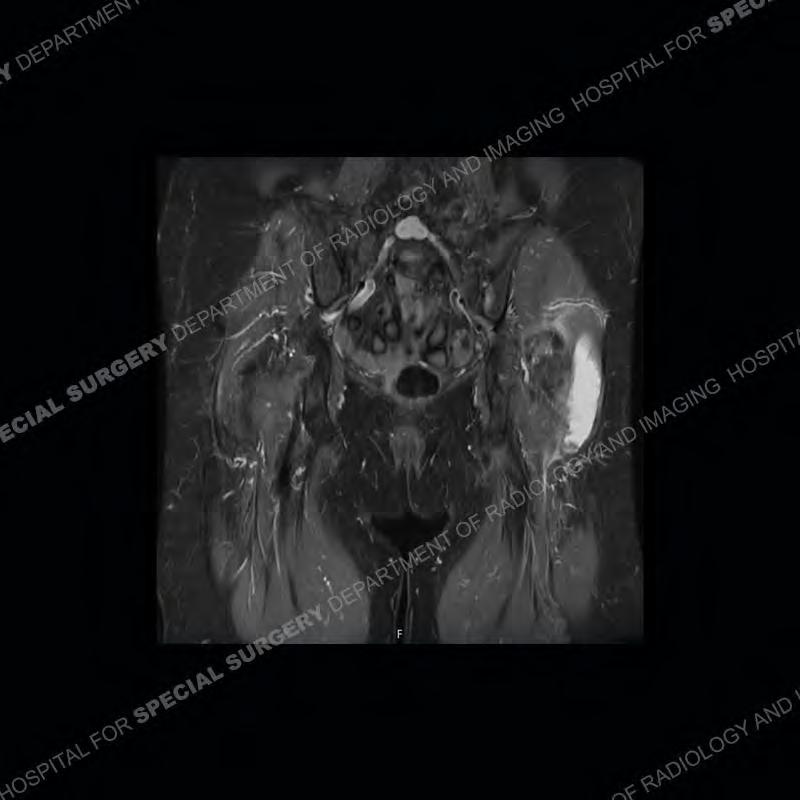

The radiograph is not particularly contributory in this case. The MRI demonstrates markedly abnormal architecture of the gluteus minimus and anterolateral band of the gluteus medius. Portions of the tendons are high signal, portions are highly attenuated, and portions are disrupted. A large, complex fluid collection is present in the adjacent soft tissue.

Diagnosis: Gluteal Tendinosis and Disruption with Complex Trochanteric Bursal Collection

Not as much of a diagnostic dilemma as many of the other cases shown but just a nice example of the pathology seen of the gluteal tendons and a cause of trochanteric pain. Although, frequently thought of in isolation, trochanteric bursitis or bursal thickening is much more commonly a reactive change to underlying pathology of the subjacent gluteal tendons. The gluteus medius is divided into a posterior band and an anterolateral band. Tendinosis and partial tearing very commonly will involve the gluteus minimus and especially the more posterior fibers and then propagate into the anterior lateral band of the gluteus medius. Involvement of the posterior band of the medius is much less common and engenders a marked degree of functional impairment.

The bursae about the greater trochanter can be a little bit confusing especially given the terminology. Trochanteric bursitis is implied to mean the subgluteus maximus bursa which is present deep to the maximus and just lateral/superficial to the trochanter. That is the bursa involved in this case. In this case the complexity of the bursa relates to the tendon tearing with inflammatory change and probably hemorrhage accounting for the complexity. Two other, less frequently involved bursa are also present. The subgluteus medius and subgluteus minimus bursa are found just deep to the named tendons. Although pathology does frequently follow the previously described pattern it is possible to have isolated pathology to either the medius or minimus.